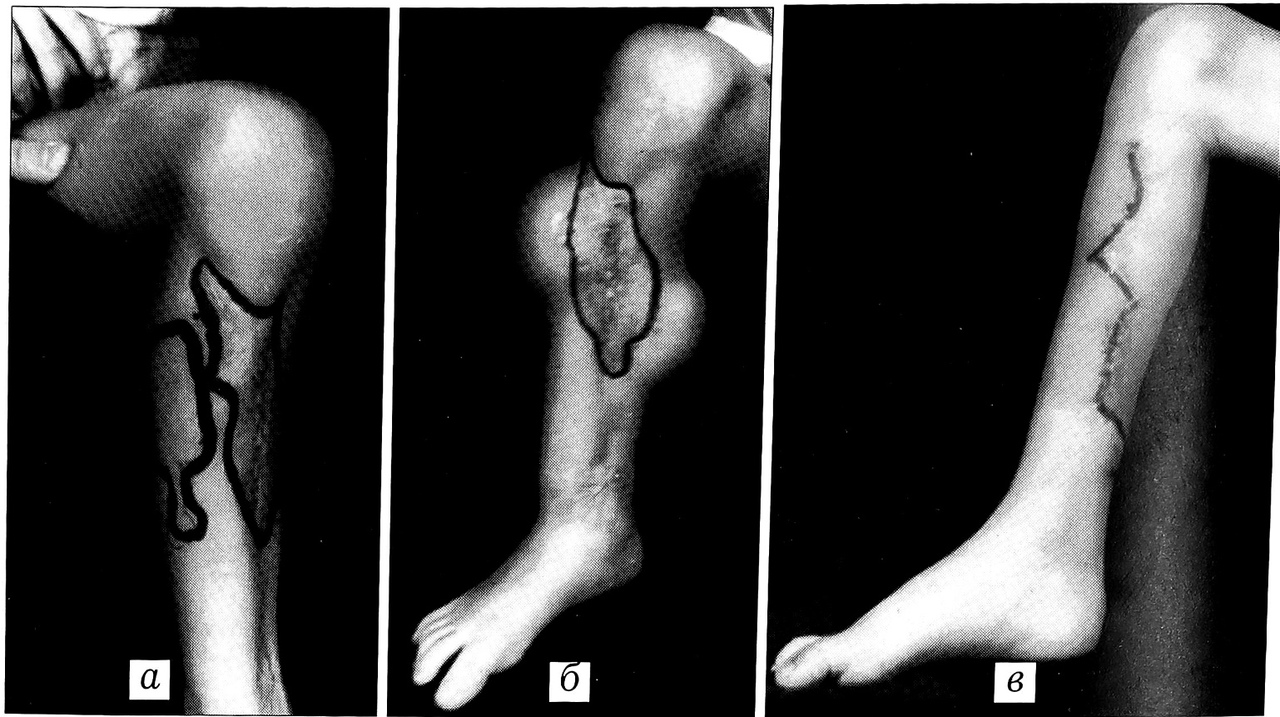

Рис. 2. Этапное восстановление полноценных кожных покровов с использованием метода эндоэкспандерной дермотензии: а - до начала лечения (рубцы по передней поверхности голени); б — в процессе эндоэкспандерной дермотензии; в — после кожной пластики.

Больная М.,12 лет, поступила с рубцовым дефектом кожных покровов, дефектом большеберцовой кости, застарелым повреждением малоберцового нерва, вторичной нейрогенной эквинусной деформацией стопы вследствие огнестрельного ранения правой голени (рис. 1).

Первым этапом имплантированы два эндоэкспандера на боковые поверхности голени с целью создания прироста кожи и последующей кожной пластики местными тканями (рис. 2). После восстановления полноценных кожных покровов произведена двухэтапная костная пластика дефекта большеберцовой кости: первый этап — закрытое наложение аппарата Илизарова для выявления истинного размера дефекта большеберцовой кости, второй этап — пластика дефекта костным аутотрансплантатом, взятым с противоположной голени (рис. 3).